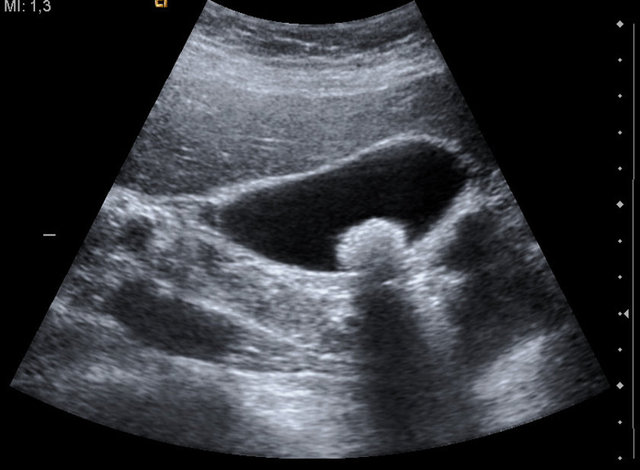

Sakarya Kamu Hastaneleri Birliği'ne bağlı Sakarya Yenikent Devlet Hastanesi'ne karın ağrısı ve karın şişkinliği şikayetiyle acil olarak müracaat eden 69 yaşındaki Nazmi Cengiz, sağlık ekiplerinin incelemeleri sonrası 18 santim uzunluğunda bir kitlenin olduğunu duyunca şaşkınlığa uğradı. Barsak tıkanıklığı ve midenin tamamını kaplayan taş kütlesini tespit eden hekimler, bunun üzerine acil ameliyat kararı aldı.

Hasta, ameliyata hazırlandığında tetkiklerinde akciğer ve kalp rahatsızlığı taşıdığı ortaya çıkınca endoskopi yöntemi düşünüldü. Ancak endoskopi yapılarak taşın çıkartılamayacağı da anlaşılınca, anestezi hekimi Dr. Burhan Kurt yüksek bölgesel anestezi uygulamaya karar verdi. Uyutulmadan ameliyata alınan hastaya Op. Dr. Zahide Kurt tarafından cerrahi müdahale başlatılarak, midenin ön yüzü tamamen açıldı. Mide içerisindeki 18 santim uzunluğunda, 10 santim kalınlığında ve 222 gram ağırlığında kabuklu ve çekirdekli yiyeceklerin sindirilmemesine bağlı oluşan taş, başarılı bir şekilde çıkartıldı.